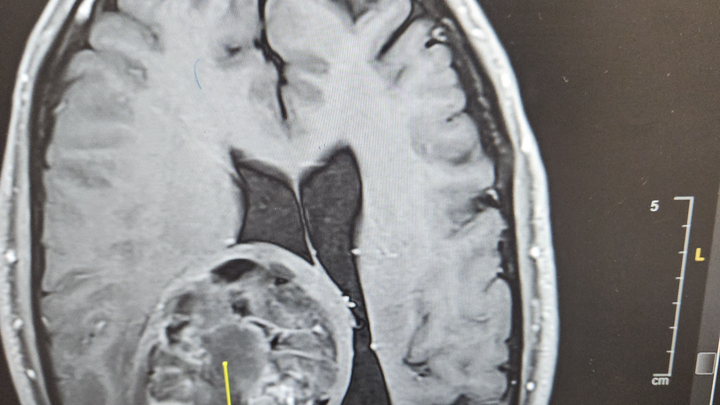

In November of 2024, I was diagnosed with a rare brain tumor called an Oligodendroglioma. Since that time, I have had two Craniotomies to remove approximately 90 percent of the tumor. The remaining tumor had crossed the midline of my brain and could not be removed. I have since undergone 30 sessions of radiation and I am now undergoing 12 months of chemotherapy.